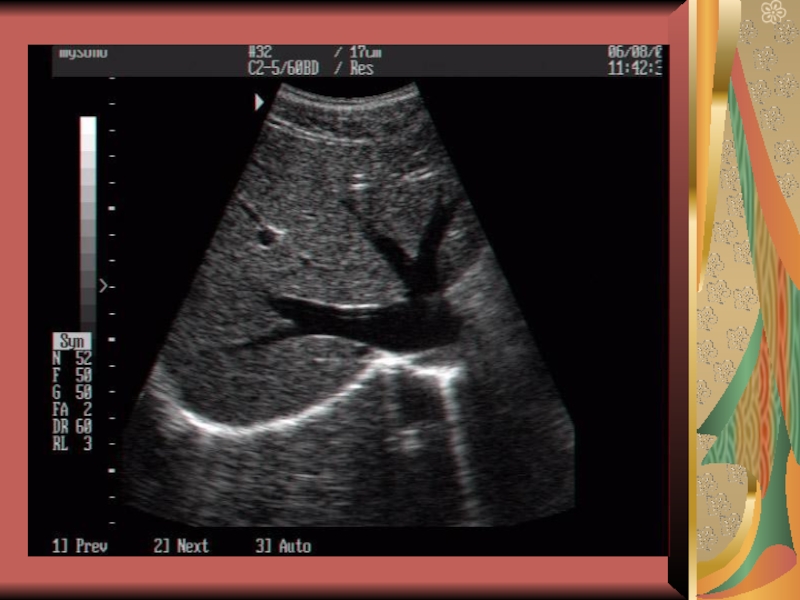

Слайд 78УЗИ брюшной полости